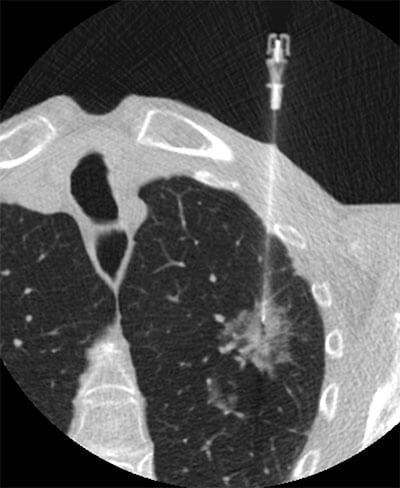

The fellowship in cardiothoracic imaging is designed for radiologists interested in furthering their knowledge of pulmonary and cardiac radiology. The fellow, under the supervision of faculty, will be guided in obtaining expertise in all aspects of clinical thoracic imaging including MRI (cardiovascular MRI and MRA), coronary CT angiography, chest CT, high-resolution CT and biopsy techniques.

The pulmonary radiology experience is also very diverse with a wide spectrum of both inpatient and outpatient referrals. UCSF has a very active interstitial lung disease clinic treating a wide range of both common and rare diffuse lung diseases. The fellow is encouraged to participate in the weekly interstitial lung disease multi-disciplinary conference with pulmonary medicine, radiology and pathology. There is also a very active inpatient clinical pulmonary medicine service that has a very close relationship with radiology and participates in weekly pulmonary consult radiology teaching sessions.